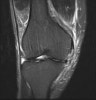

MRI : 무릎 내측 측부인대 손상(Medial collateral ligament injury, MCL injury)

MRI는 보다 정확한 병적상태를 파악하는 데 도움을 줍니다.